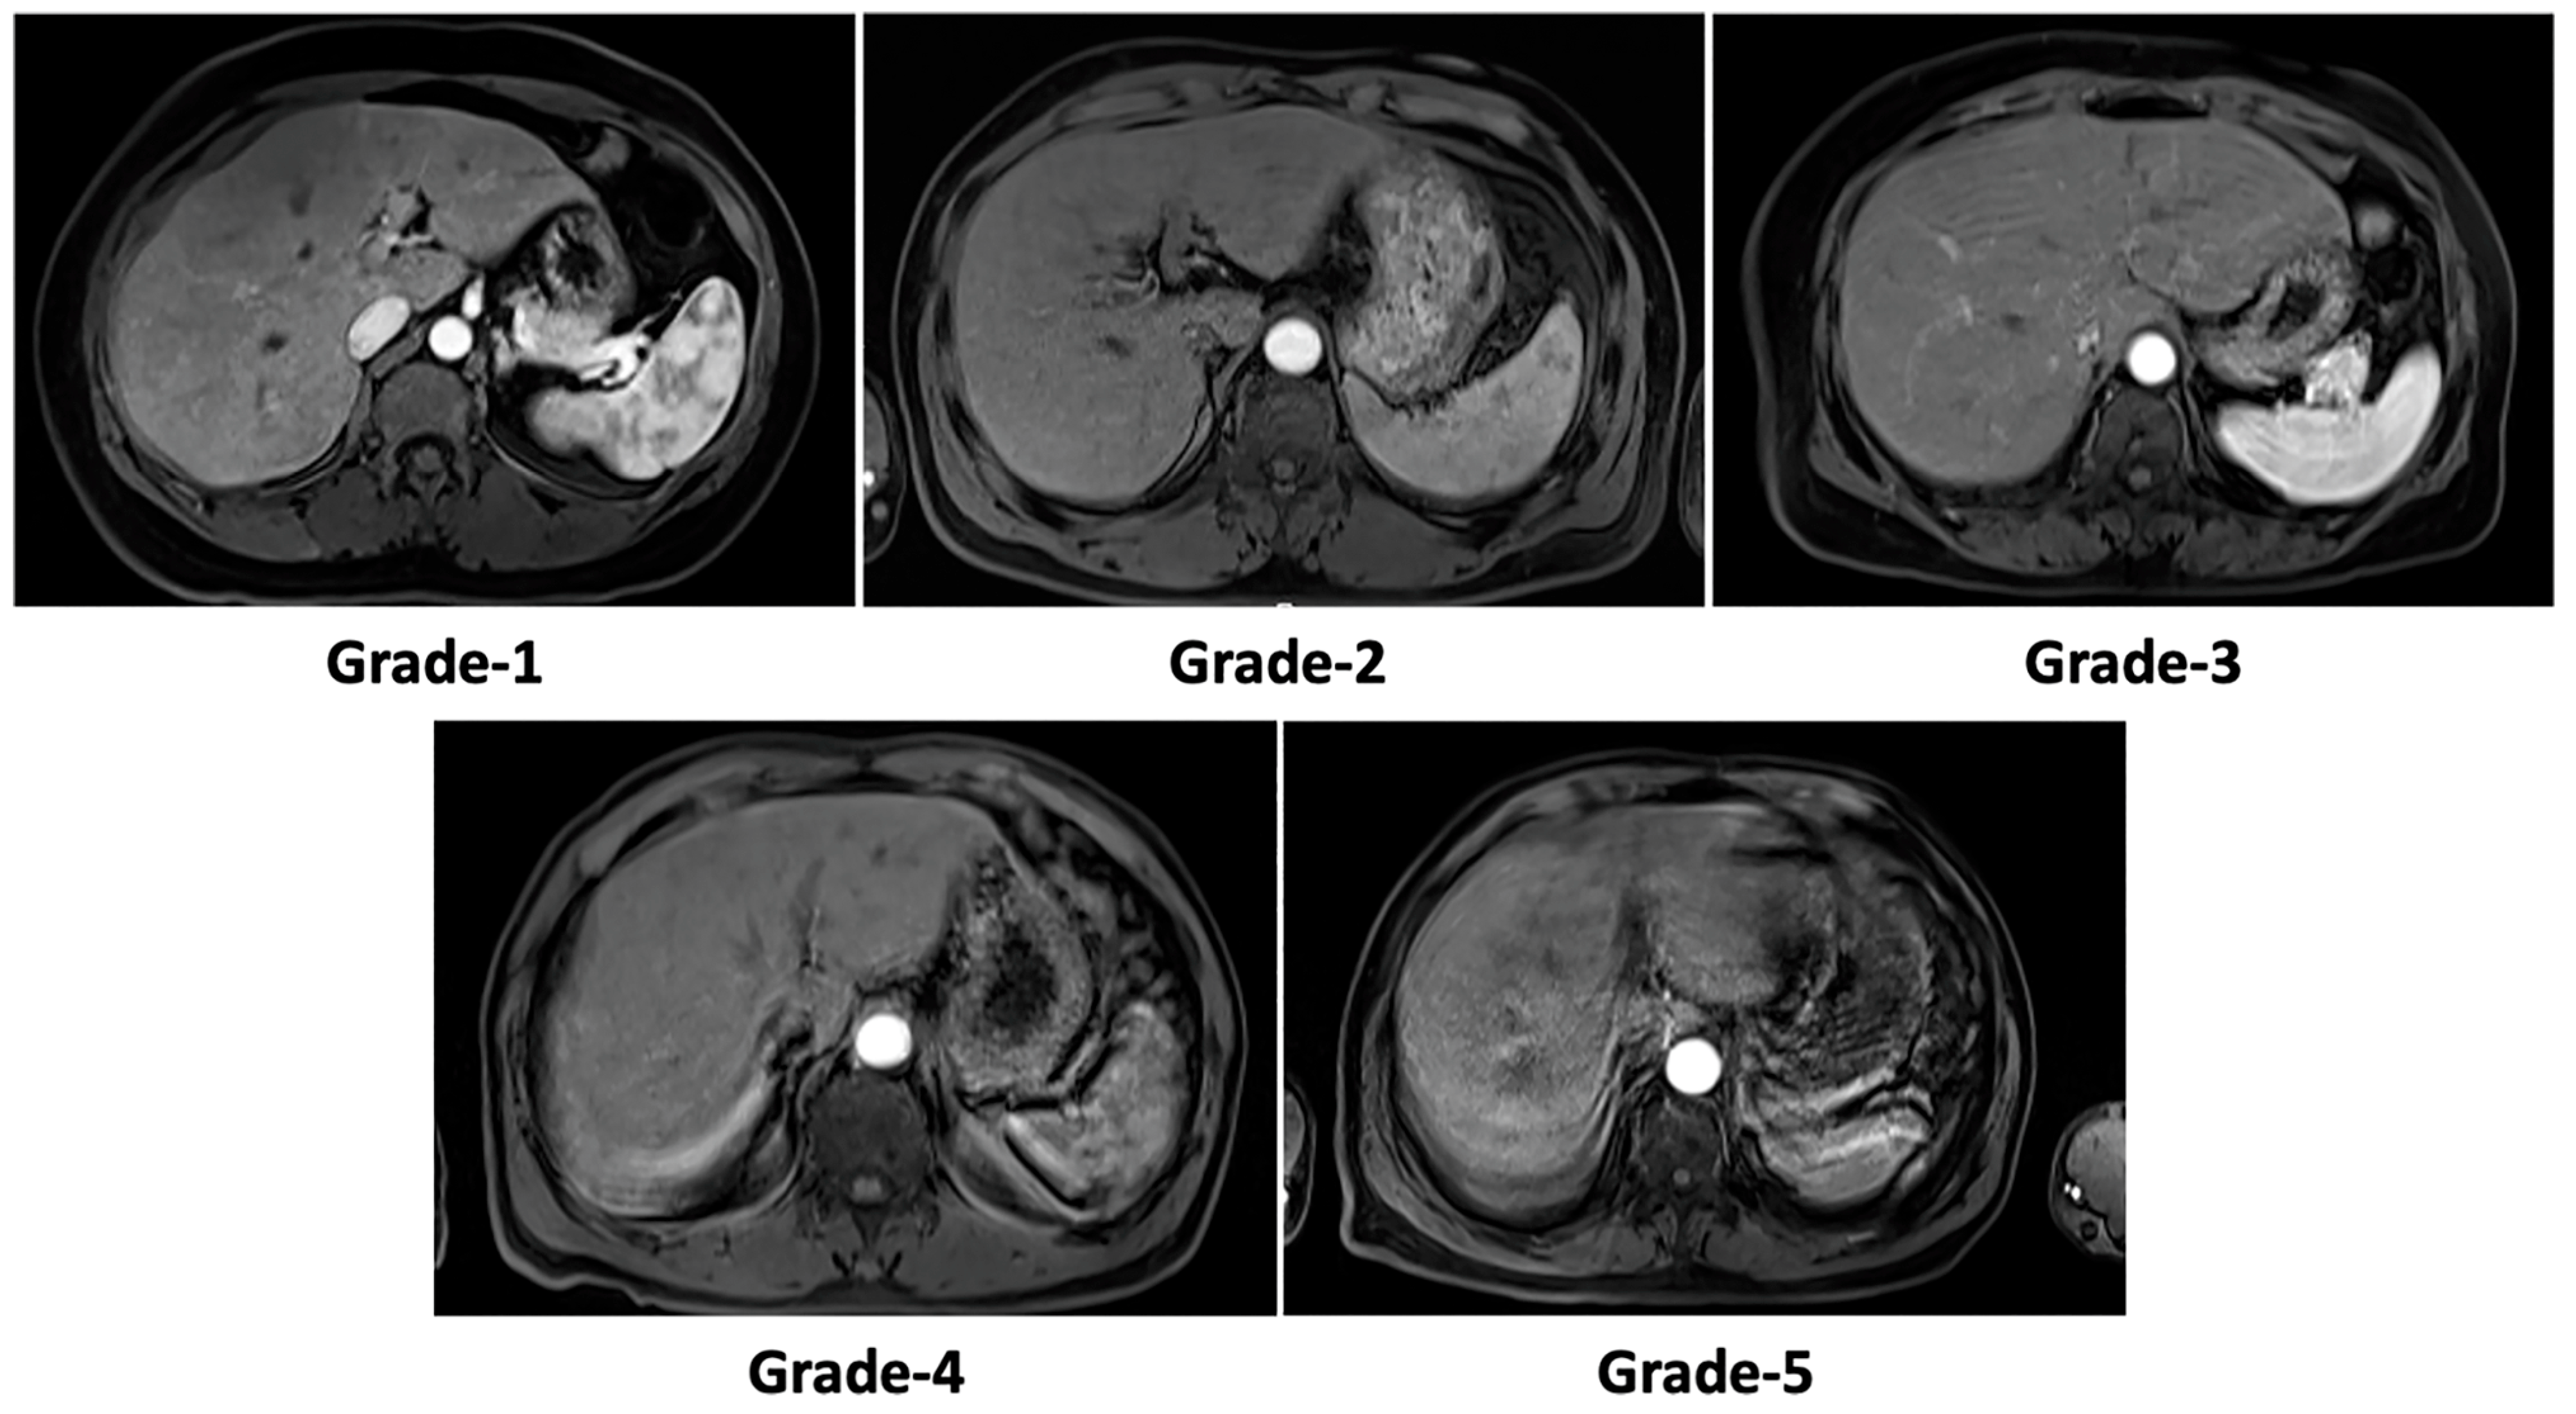

2.3. Motion Artifact Grading